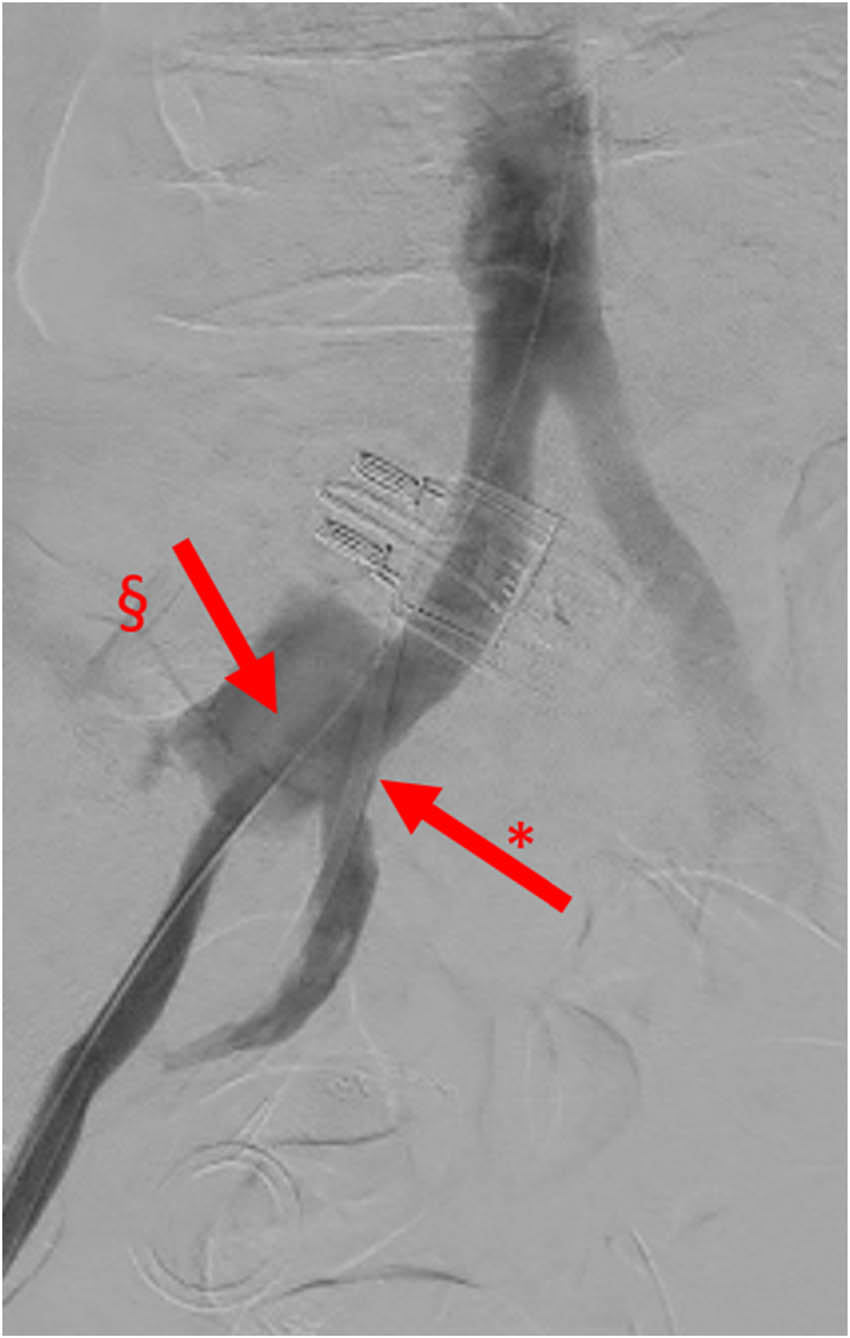

Figure 3

Angiography, image with no digital subtraction, frontal view, late arterial phase, case 1. Iodinated contrast leakage from UAF. *: right ureteral double J stent and §: contrast leakage from UAF.

Subiela et al. reported the number and type of diagnostic techniques used in the most recent studies from 1990 to 2017: the prevalence of angiography and angioTC employment was 36.2 and 29.8%, respectively, but the authors did not refer their diagnostic accuracy. However, the authors stated that CT scan with contrast was the most used and accurate method for the diagnosis of UAF [10]. In our first case, the indication for CT scan was mandatory due to the lipothymic-neurological signs that anticipated the severe haemorrhagic shock. CT scan in this case was diagnostic, and angiography only confirmed and targeted the fistula for the endovascular treatment. The antegrade pyelography carried out after endovascular treatment was purely descriptive. The positivity of all radiological exams is certainly attributable to the size of the fistula (6 mm in maximum diameter) which, in the acute phase of rupture, determined a blood outflow of about 7 mL/s, considering that usually the speed of blood flow at the level of the iliac artery is about 30 cm/s.